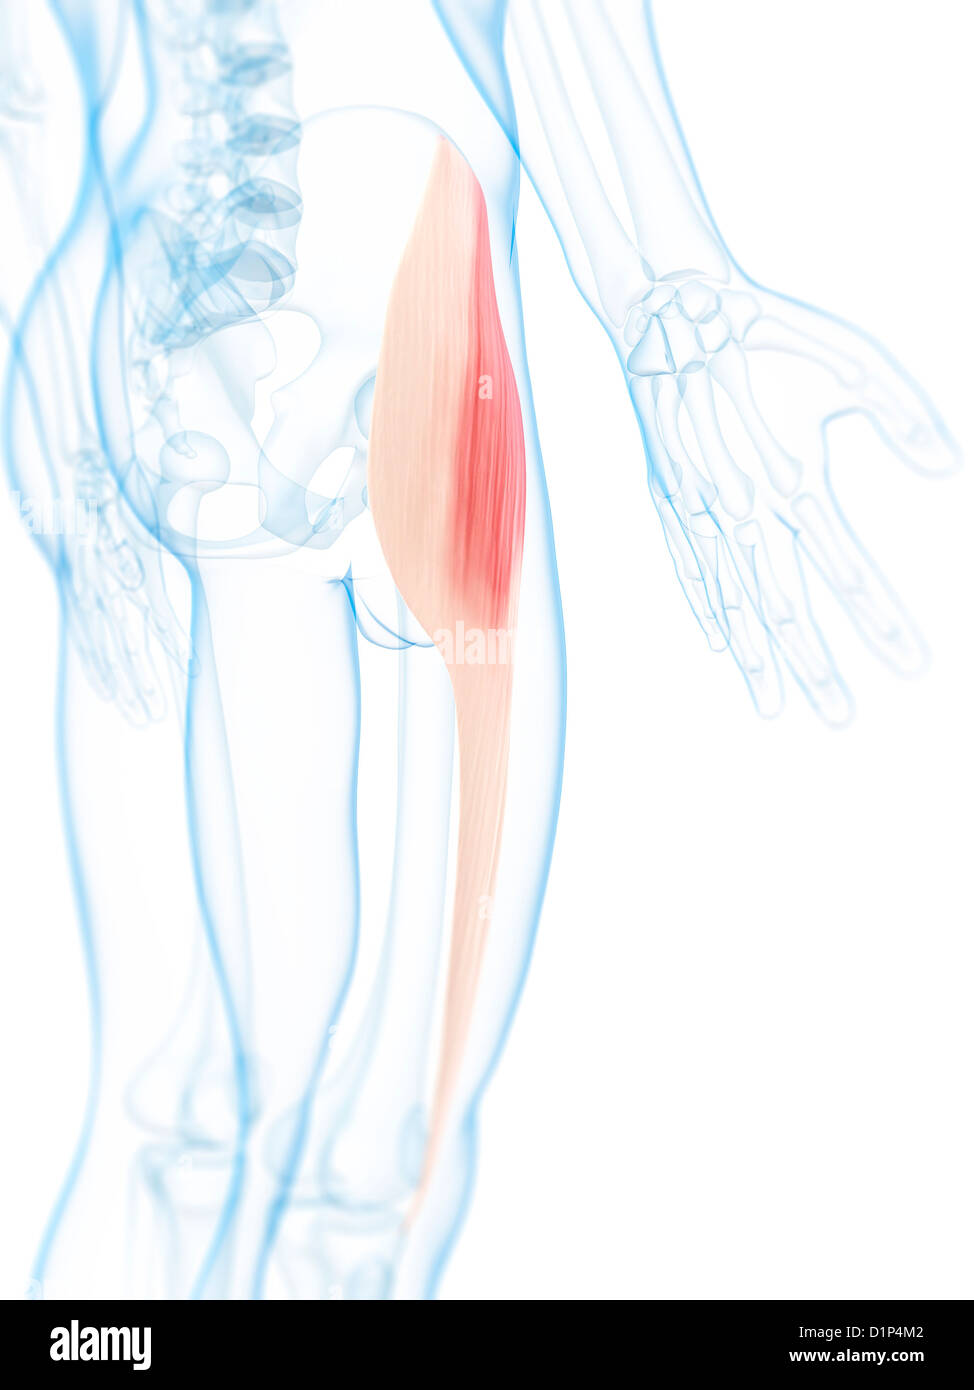

Thigh muscle, artwork Stock Photohttps://www.alamy.com/image-license-details/?v=1https://www.alamy.com/stock-photo-thigh-muscle-artwork-52732402.html

Thigh muscle, artwork Stock Photohttps://www.alamy.com/image-license-details/?v=1https://www.alamy.com/stock-photo-thigh-muscle-artwork-52732402.htmlRFD1P4M2–Thigh muscle, artwork